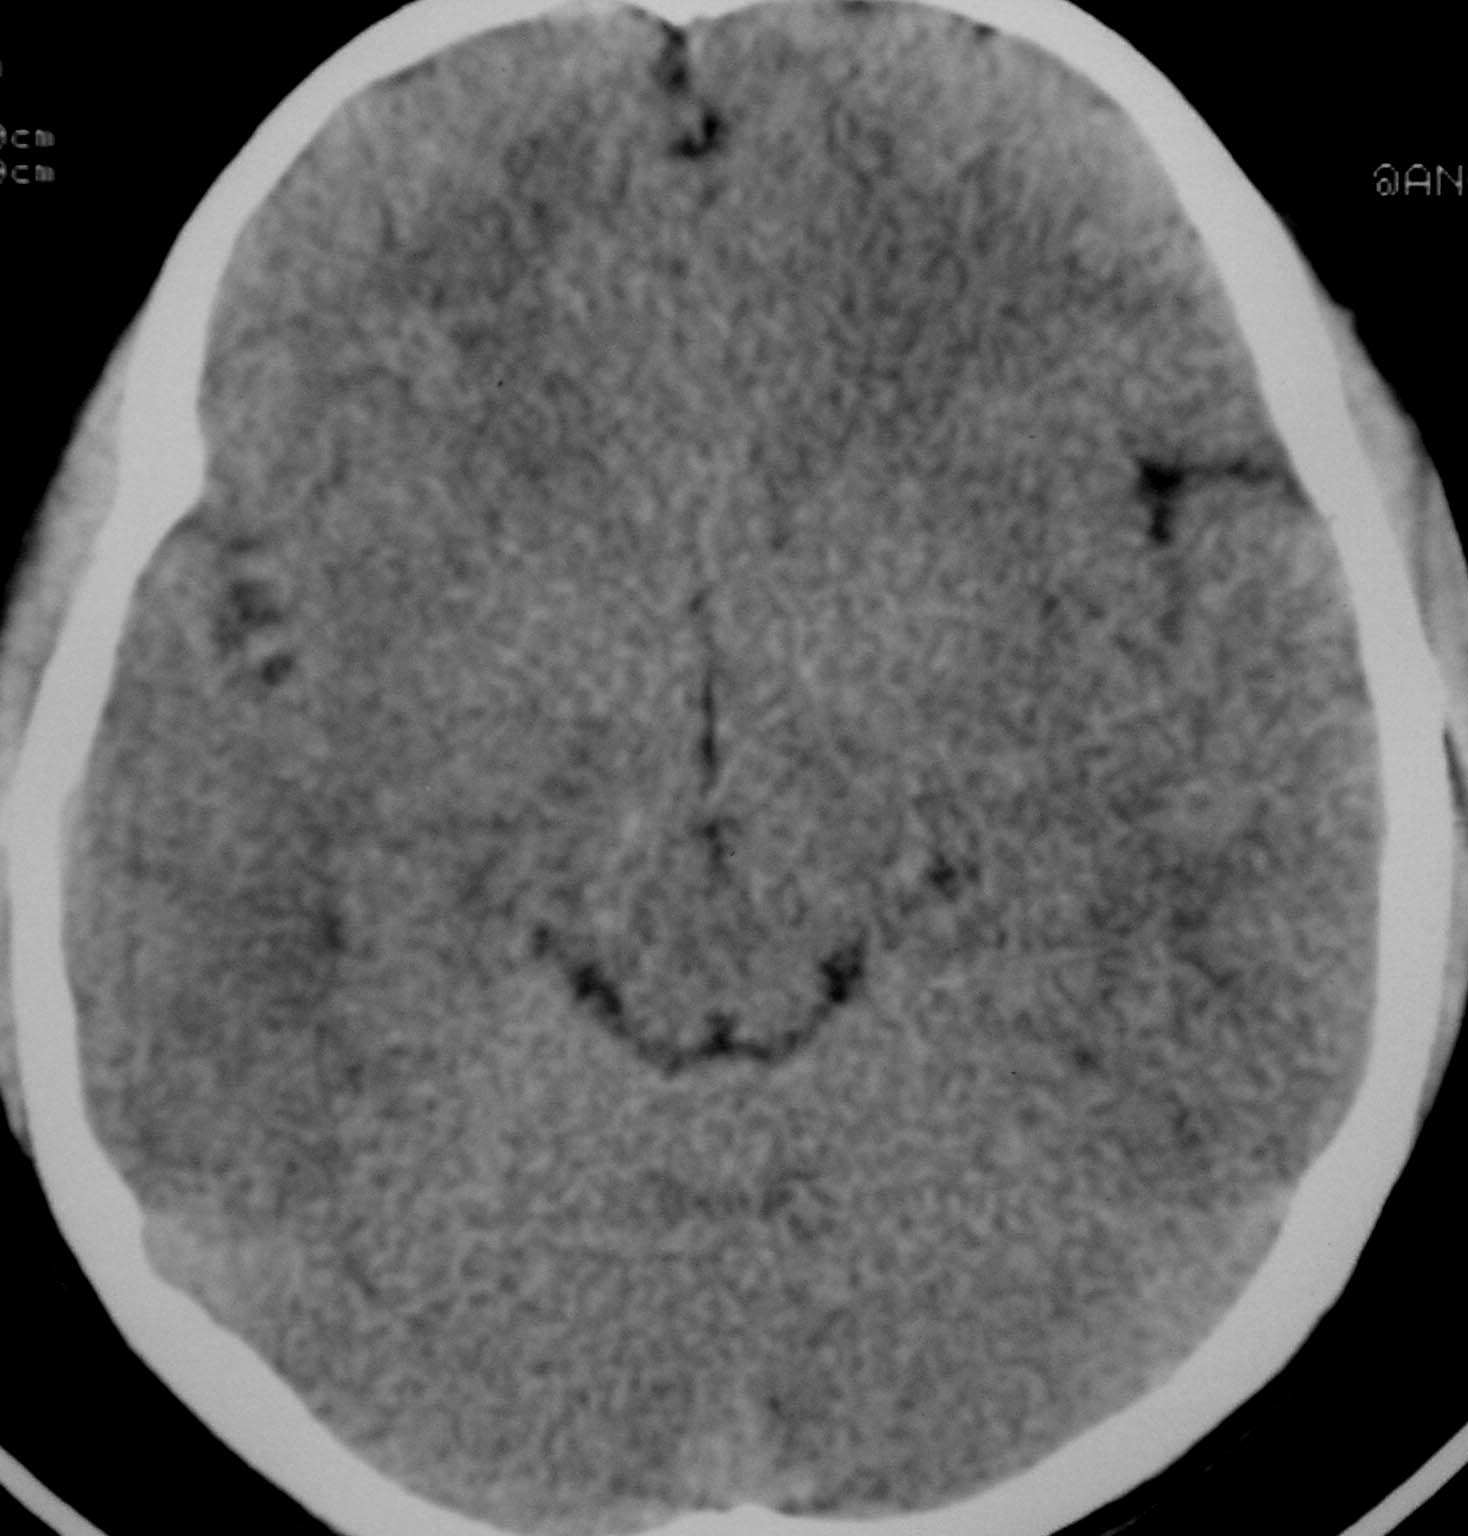

以下是引用余辉在2007-4-28 19:55:00的发言:[br]血管畸形?增强一下

以下是引用jw-830在2007-4-28 20:22:00的发言:[br]考虑血管畸形可能建议增强

以下是引用ysxyy在2007-4-29 21:14:00的发言:[br]像是假像,如果不放心可以偿试一下:[br]你用听眦线为基线扫一下,再用听眶线扫一下,就是说用不同的角度扫同一个地方;[br]看看有无变化,是不是有相同或相似的表现,即可鉴别;